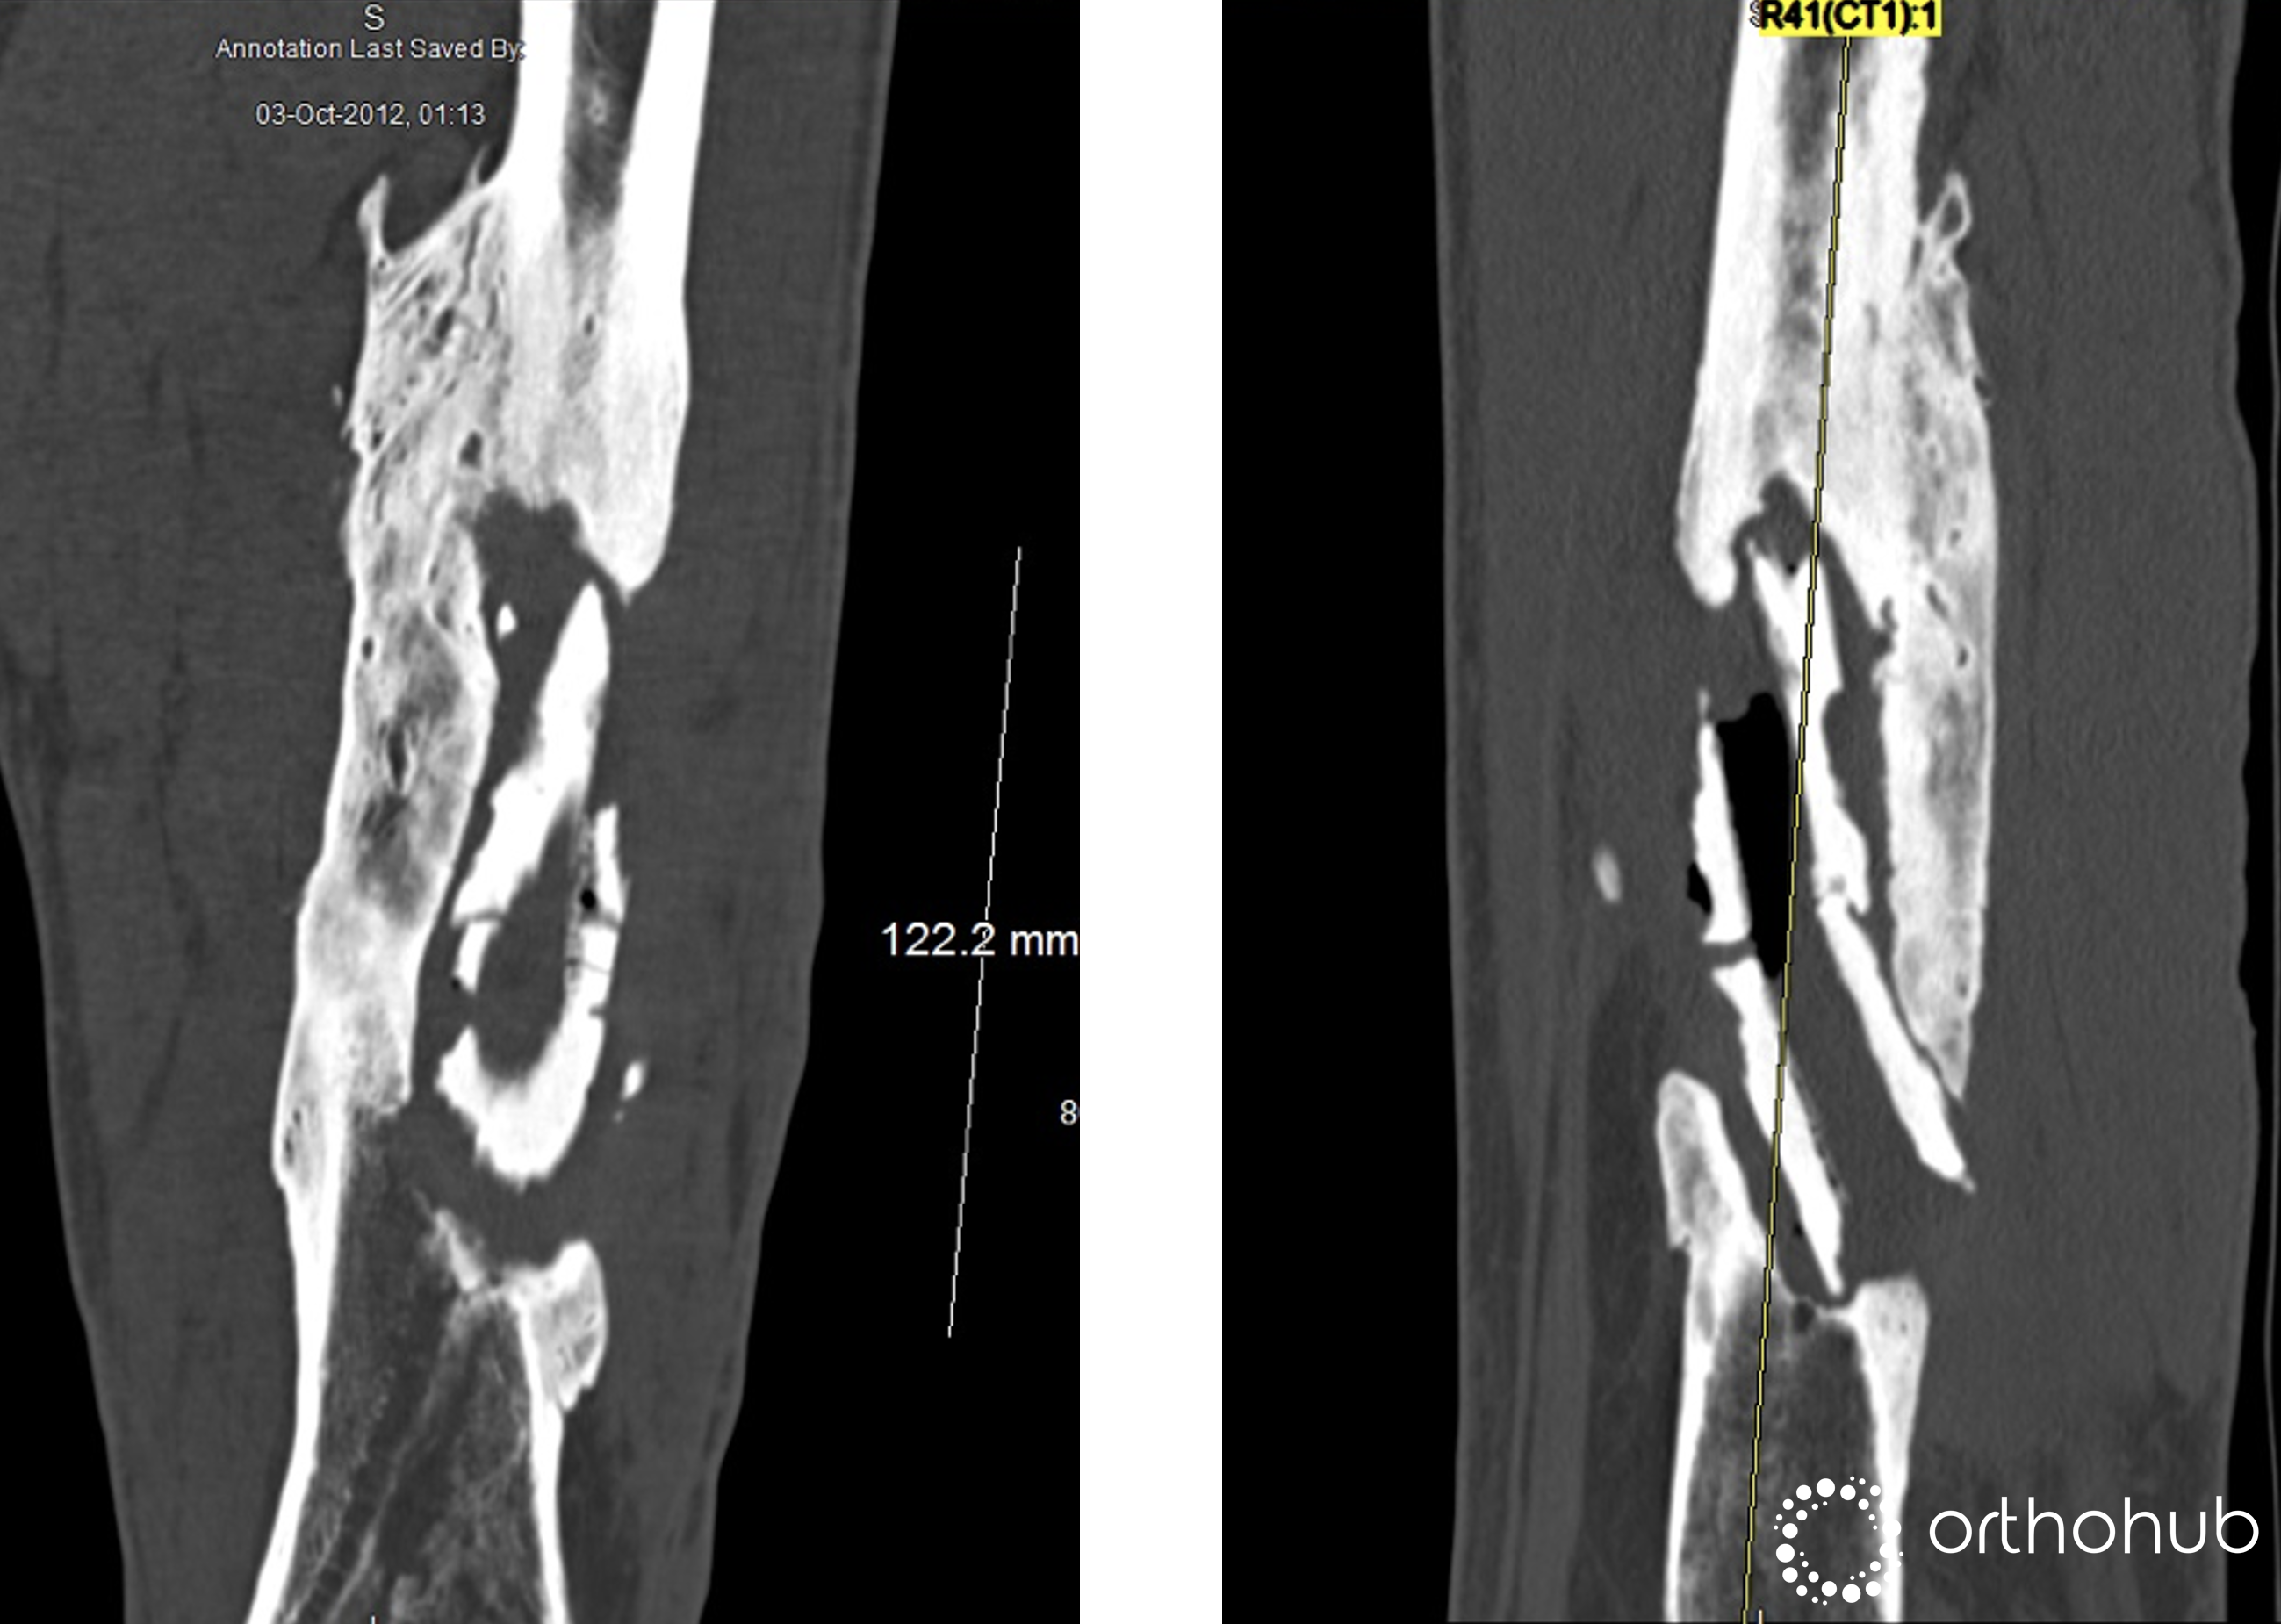

49 year old male who had an open fracture of the left femur in Morocco 20 years previously. Which was treated non-op.

Since then, he's had on/off local drainage and periods of antibiotics

CT Scan